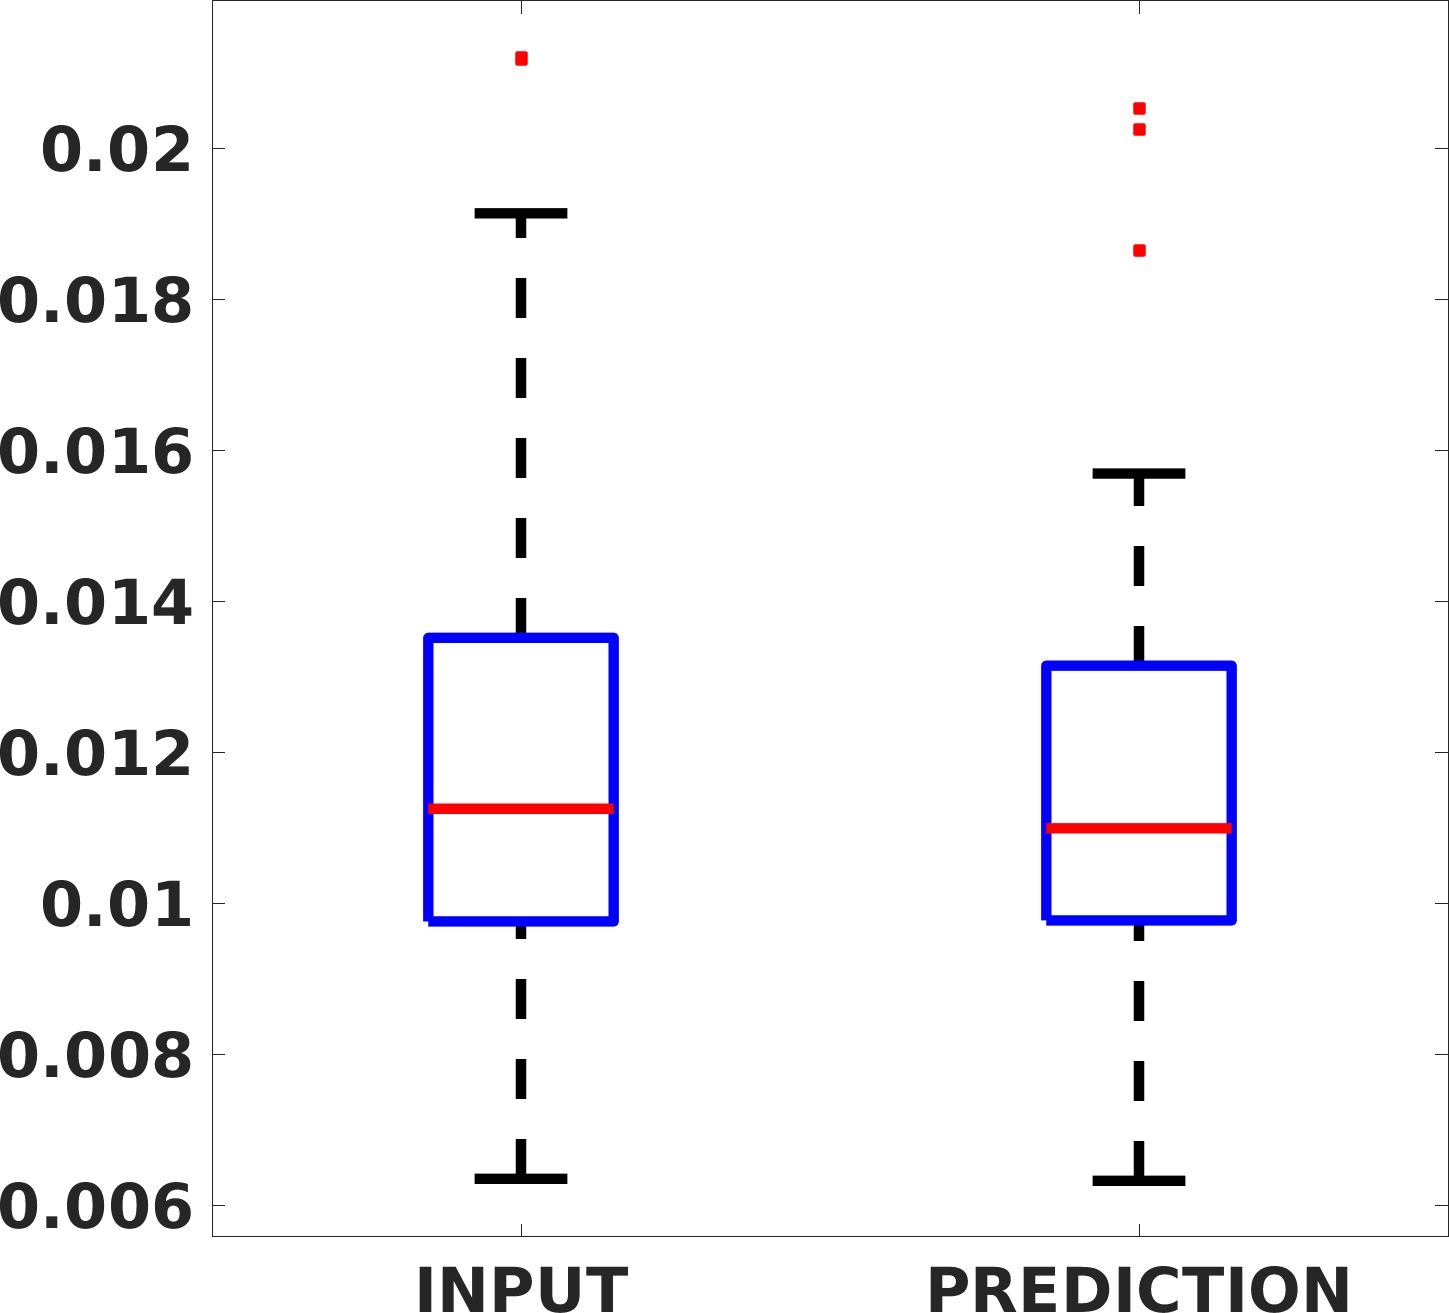

Fig. 7(a-b-c, left) shows the box plot of the statistics of the PSNR on three different anatomical districts, comparing the target images with the prediction and the cubic convolution, respectively. The metrics are computed on a data set of 200 images of the same district and with the same up-sampling factor. We report that the PSNR median value improves of on obstetric 2X raw images, on cardiac 2X raw images, and on abdominal raw 4X images.

Fig. 7(a-b-c, right) shows the histogram of the absolute value of the error with respect to the target image, of the prediction and Cubic convolution results, respectively. The histograms show the number of pixels where the prediction error is lower than 5 (i.e., the first bin of the histogram), which means very similar to the target when visually analysing the images. From the Cubic convolution to the predicted images, this value increases of on obstetric 4X raw images, on cardiac 4X raw images, and on abdominal 4X raw images.

Fig. 8 shows the box plot of the SSIM (a-b-c, left) and MAE (a-b-c, right) quantitative metrics, as performed for PSNR metric. Also, these metrics show that our method improves the results of Cubic convolution both in terms of average value and variability. For example, the SSIM median value improves of on obstetric 4X images and the MAE median value improves of on cardiac 2X images.